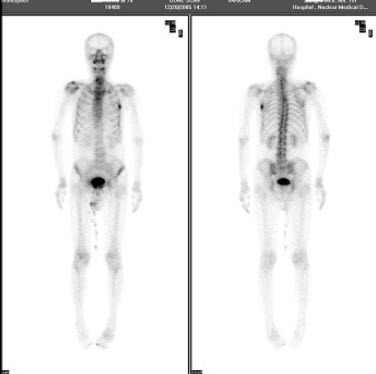

13、多项选择题

一男性病人的99Tcm-MIBI运动-静息心肌灌注显像如图,可能的诊断是()

A.左心室无心肌缺血

B.左心室前壁缺血

C.左心室心尖缺血

D.左心室前侧壁缺血

E.左心室后壁缺血